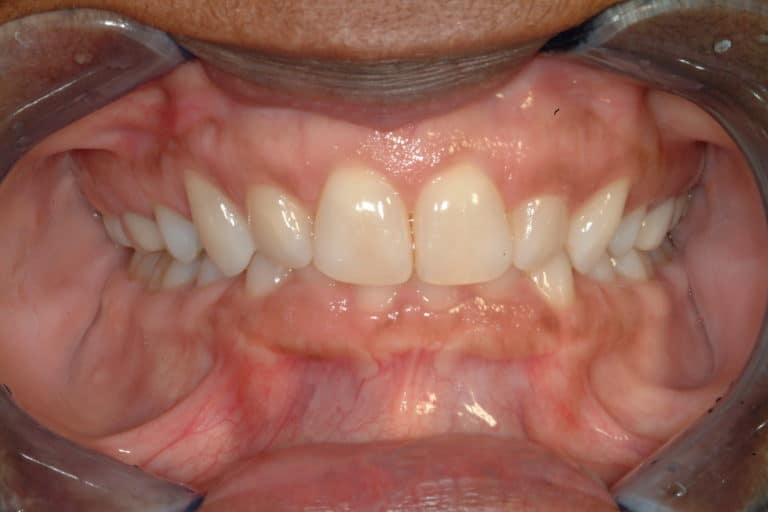

Before & After Gallery

Individual results may vary.